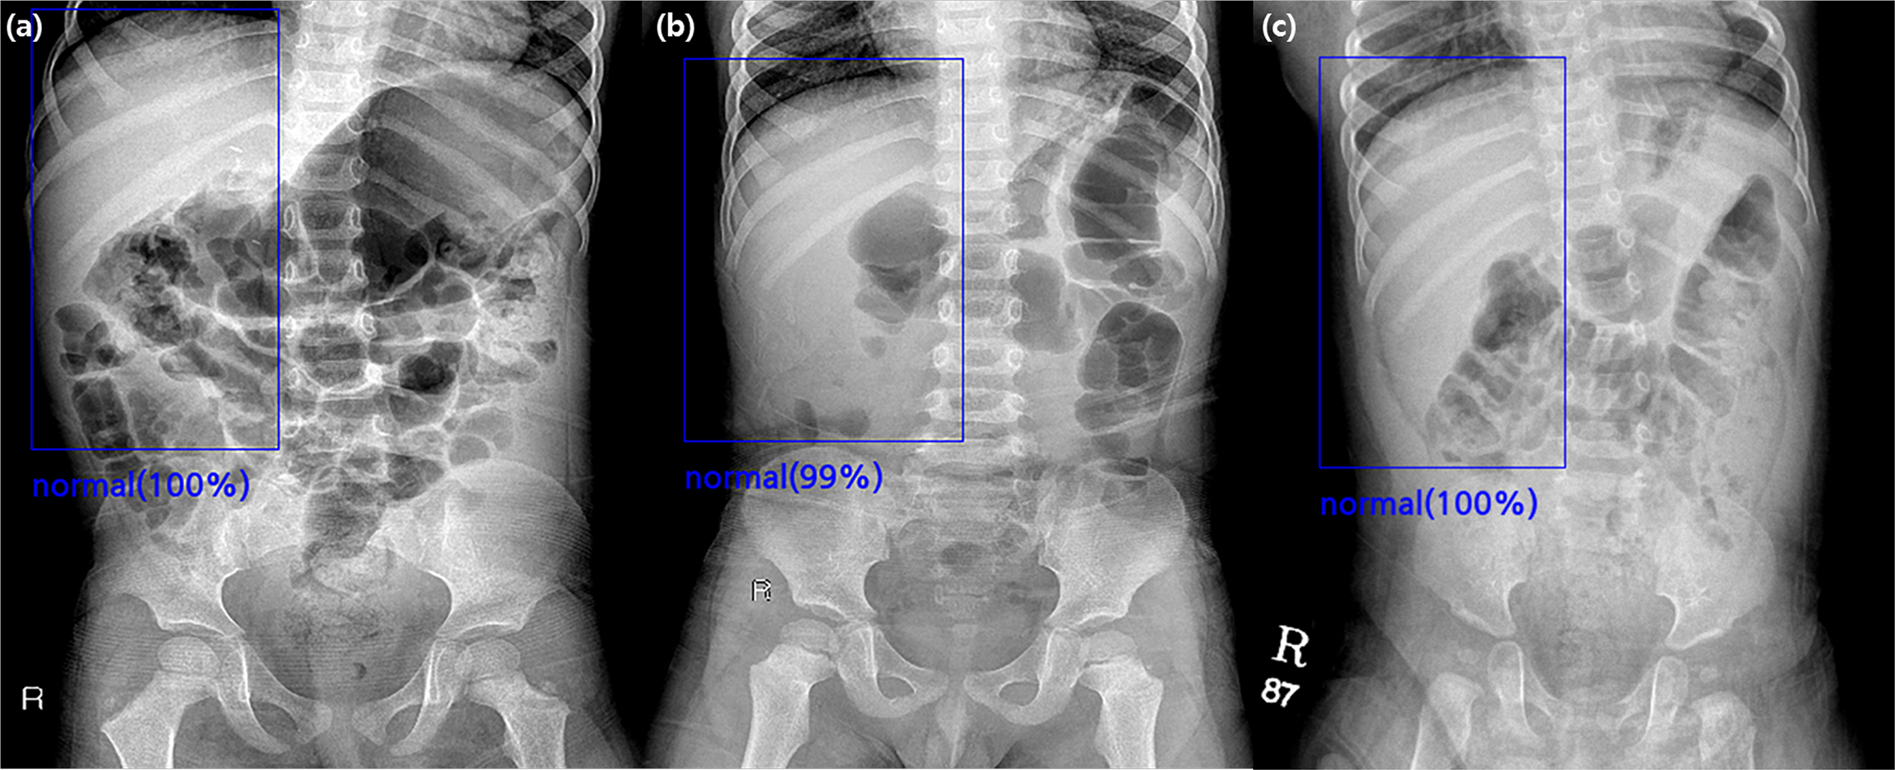

Figure 2

True-negative cases found by the algorithm in the validation set. (a) A supine abdominal radiograph of a 36-month-old girl without intussusception. All four radiologists and the algorithm reported true-negative results because there was no round opacity obscuring bowel gas in the right abdomen. (b) A supine abdominal radiograph of a 48-month-old boy without intussusception. Two radiologists reported false-positive results, while the algorithm and the other two radiologists reported true-negative results. (c) A supine abdominal radiograph of an 11-month-old boy without intussusception. Four radiologists and the algorithm all reported true-negative results.